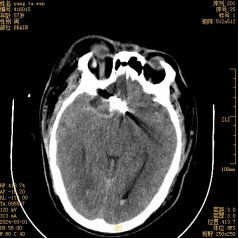

術(shù)后復查頭顱CT提示:顱腦結構正常,顯示清楚,環(huán)池、側裂池及縱裂池蛛網(wǎng)膜下腔出血明顯減少(術(shù)中進(jìn)行了清除),動(dòng)脈瘤夾位置良好(如箭頭所示)。